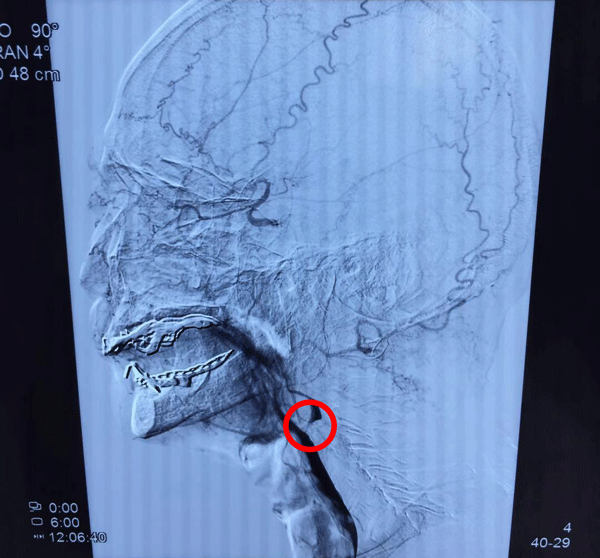

匡老,来自于安徽省六安市,8个月前逐渐发现左侧肢体活动不灵活,持物及站立不稳。左侧颈动脉超声:残余内径1.6mm,原始内径8.1mm,流速207cm/s。以“右侧颈动脉闭塞、左侧颈动脉重度狭窄(NIHSS评分4分)”入院。

患者的右侧颈动脉已经闭塞,几乎仅靠左侧颈动脉向脑部供血,但左侧也是重度狭窄,一旦左侧进一步狭窄,性命将受到威胁。

手术中发现:患者的左侧颈动脉存在很多的溃疡斑块、病变。不过,这可难不住张勤奕教授,他逐渐取出拥堵在患者血管里的斑块、缝合血管、清理患处等,让患者的颈动脉有更多血液流向大脑。